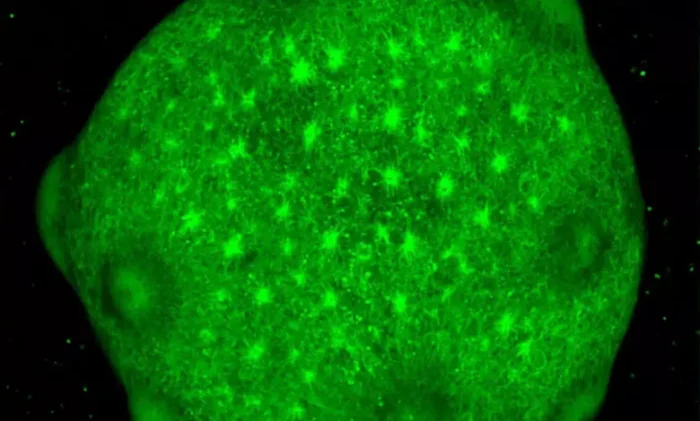

По мере развития органоиды мозга становятся все более сложными. Со временем они содержат многие типы клеток, встречающиеся в человеческом мозге, и демонстрируют пространственную организацию, сравнимую с изолированными областями мозга. Опять же, хотя иногда их называют «мини-мозгами», эти органоидные структуры мозга на самом деле не являются миниатюрными человеческими мозгами. Представьте себе сферические шары из ткани, которые имитируют некоторые особенности человеческого мозга.